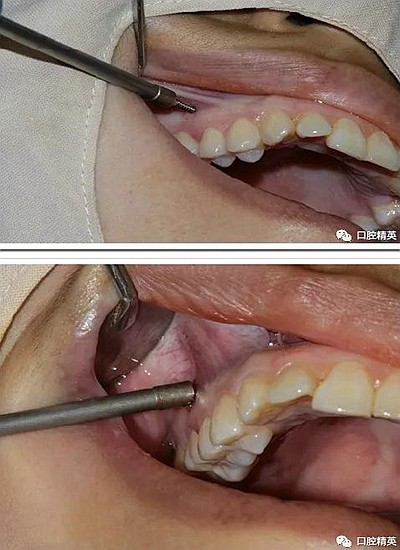

再次,植入微型種植體,在附著牙齦處不需要粘骨膜翻瓣,在牙槽黏膜處則需要切開(kāi)黏膜以避免植入時(shí)軟組織被卷入,植入部位通常在膜齦結(jié)合部位或偏根方2~3mm,植入角度與骨面垂直并傾斜15~20度,即向根尖方向植入,術(shù)后拍根尖片以確認(rèn)與牙根的關(guān)系。術(shù)后口服抗生素預(yù)防感染并進(jìn)行口腔衛(wèi)生宣教。

2、助攻型種植釘,上頜與頜骨成30-40°角,下頜與頜骨成10-20°角(目的:1、降低損傷牙根及牙周膜的機(jī)率;2、使種植釘盡量植入骨皮質(zhì)內(nèi),降低松動(dòng)機(jī)率);自攻型種植釘與頜骨垂直;個(gè)人習(xí)慣:自攻型種植釘上下頜均與頜骨成30-40°角。

3 、無(wú)論是助攻型還是自攻型種植釘,植入前分離粘骨膜步驟必不可少。軟組織的夾入是手術(shù)失敗的常見(jiàn)原因之一。

4 、植入時(shí),旋轉(zhuǎn)速度盡量慢,防止因產(chǎn)熱過(guò)多使組織變性,影響釘骨愈合;旋入時(shí)手盡量穩(wěn),防止洞口直徑過(guò)大于種植釘直徑。